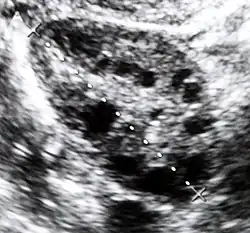

Polycystic ovary syndrome accounts for about 70% of hyperandrogenism cases.[1] Other causes include Congenital adrenal hyperplasia, insulin resistance, hyperprolactinemia, Cushing's disease, certain types of cancers, and certain medications.[4][1][3] Diagnosis often involves blood tests for testosterone, 17-hydroxyprogesterone, and prolactin, as well as a pelvic ultrasound.[1][4]

Polycystic ovary syndrome (PCOS) is an endocrine disorder characterized by an excess of androgens produced by the ovaries. It is estimated that approximately 90% of women with PCOS demonstrate hypersecretion of these hormones.[19] The cause of this condition is unknown. Speculations include genetic predisposition; however, the gene or genes responsible for this remain unidentified.[20] The condition may have a hereditary basis. Other possible causes include elevated insulin production. Most cases of PCOS involve insulin resistance.[21] It is thought that adipose tissue dysfunction plays a role in the insulin resistance seen in PCOS.[21] Insulin can induce excess testosterone secretion from the ovaries.[22] A complication associated with polycystic ovary syndrome is high cholesterol, which is treated with statins. In a meta-analysis, atorvastatin was shown to decrease androgen concentrations in people with hyperandrogenism.[23]